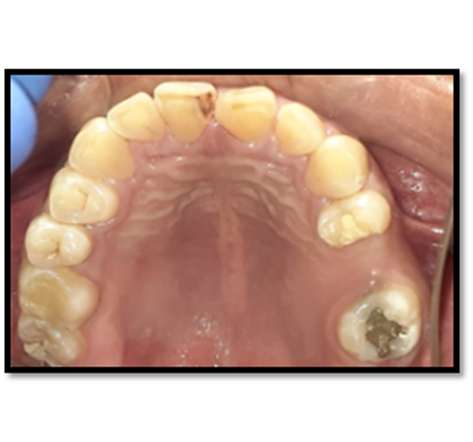

El estudio radiográfico puede evidenciar múltiples sombras radiopacas rodeadas de un halo radiolúcido pertenecientes a un tumor odontogénico CIE10: D164 (odontoma compuesto), localizados en a nivel de los órganos dentarios 4.3; 4.1; 3.1; 3.2; 3.3. También se puede constatar la presencia de una sombra radiopaca que concuerdan con el órgano dentario retenido.

Imagen 2. Radiografica Panorámica.

En su gran mayoría en la presentación de este caso clínico se puede observar la presencia de una sombra radiopaca que concuerdan con el órgano dentario retenido 4.2.con una imagen mixta con múltiples radiopacidades muy similares a los órganos dentarios que están rodeados de un halo radiolúcido perimetral que son similares descripciones de investigaciones de otros autores.